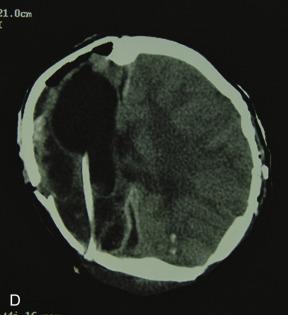

This 19-year-old male lost control of his bicycle on a wet bridge and was run over by a truck ( Fig. 3.1.2 ). After debridement of his compound right fronto-orbital defect, along with complete removal of the remnants of his frontal sinus (proper neurosurgical treatment), he was left with the defect shown, which was easily repaired with split calvarial bone from adjacent parietal bone.